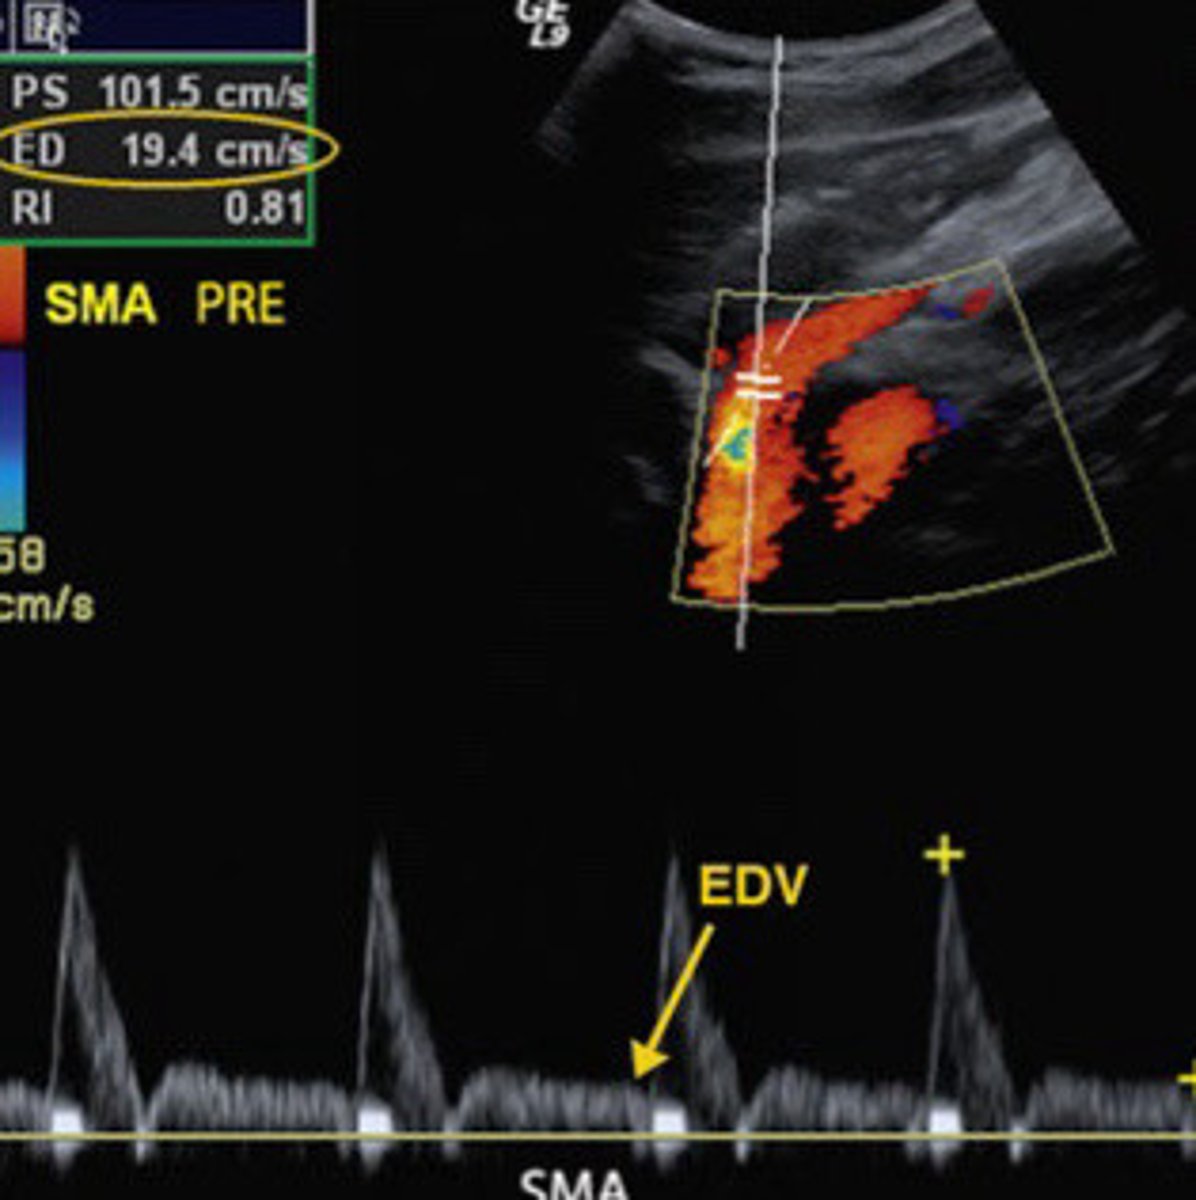

Describe the waveform seen in the SMA when the patient is in a fasting state

Pre prandial

What is another term for fasting

Fasting/preprandial (higher resistance, can see dicrotic notch and not a lot of diastolic flow)

Is this image taken form the SMA most likely from a patient who is pre-prandial or post-prandial